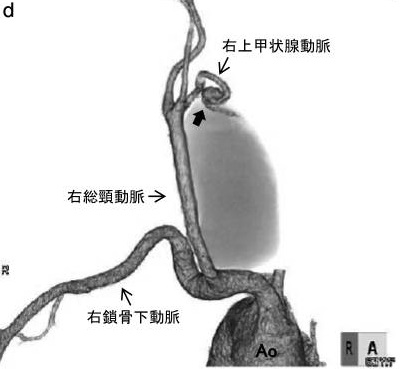

大動脈留だけではありません。動脈硬化による動脈瘤は、甲状腺を栄養する動脈にも起こります(日血外会誌 15:517-519,2006)。上甲状腺動脈瘤、下甲状腺動脈瘤で、これまでに40例未満の報告しかありません。大きさは0.8~6.2cmと様々で、大きさと破裂の有無とは関連しません。

甲状腺動脈瘤以外の末梢動脈瘤は、血栓塞栓症が多く、破裂は稀とされます。しかし、甲状腺動脈瘤で血栓塞栓症をおこした報告はありません。甲状腺動脈瘤報告例で、破裂の割合は下甲状腺動脈瘤58.3%、上甲状腺動脈瘤25%、破裂瘤の20%は死亡しています。

甲状腺動脈瘤で破裂が多いメカニズムは不明です。 破裂前に見つけて無症候性(症状が無い)でもコイル塞栓術、あるいは外科的切除(甲状腺の一部を同時切除もあり)を早急に行う必要があります(内分泌甲状腺外会誌 31(3):243-246,2014)。元々、甲状腺手術予定があるなら、同時に切除もあり得ます。

甲状腺腫瘍を穿刺吸引細胞診する際、甲状腺動脈の外膜を傷付けて仮性動脈瘤が発生する事があります。動脈硬化した硬くて脆い所が動脈瘤に成り易いとされます。破裂すると命にかかわるため、コイル塞栓術、あるいは外科的切除(甲状腺の一部を同時切除もあり)を早急に行う必要があります。[J Ultrasound Med. 2004 Dec;23(12):1675-8.]